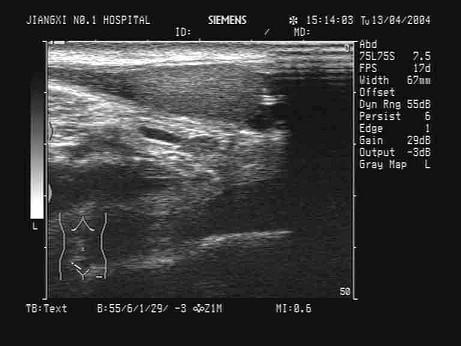

某小儿其右腹股沟区B超检查声像图如图,最可能的诊断为?(?)A.隐睾B.肿大淋巴结C.正常腹股沟声像图D.盆腔肿瘤E.斜疝

问题 某小儿其右腹股沟区B超检查声像图如图,最可能的诊断为?(?)

选项 A.隐睾 B.肿大淋巴结 C.正常腹股沟声像图 D.盆腔肿瘤 E.斜疝

答案 A